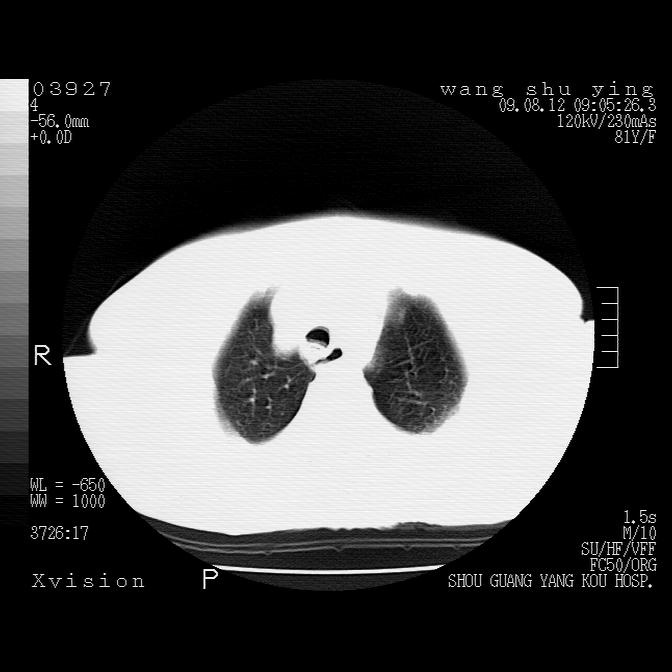

以下是引用帅河马在2009-8-12 12:59:00的发言:[br]两肺感染性病变伴双侧胸膜肥厚。[br]左侧甲状腺腺瘤不除外。[br]腹水+心包积液。[br][br][本贴已被 帅河马 于 2009-8-12 13:14:32 修改过]

以下是引用sdzyy在2009-8-12 18:17:00的发言:[br]两肺感染性病变伴双侧胸膜肥厚。[br]左侧甲状腺腺瘤不除外。[br]腹水+心包积液。[br]支持

以下是引用随光逐影在2009-8-12 19:42:00的发言:[br]1)两肺感染性病变伴双侧胸膜肥厚。2)不排除左侧甲状腺腺瘤。3)肝脏占位性病变;建议行进一步检查。